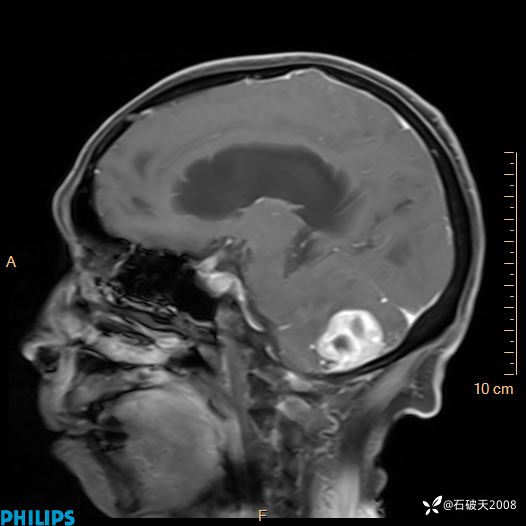

增强矢状位